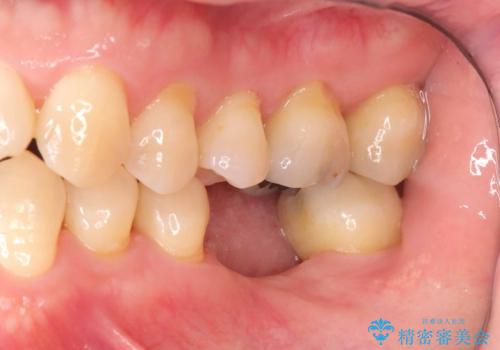

- レントゲン検査にて、根尖および側枝付近に骨の透過像が認められました。

さらに精査したところ、根のパーフォレーション(根に穴が開いてしまっている状態)が確認されたため、

患者様と相談のうえ、インプラントによる治療をご希望され治療を行いました。